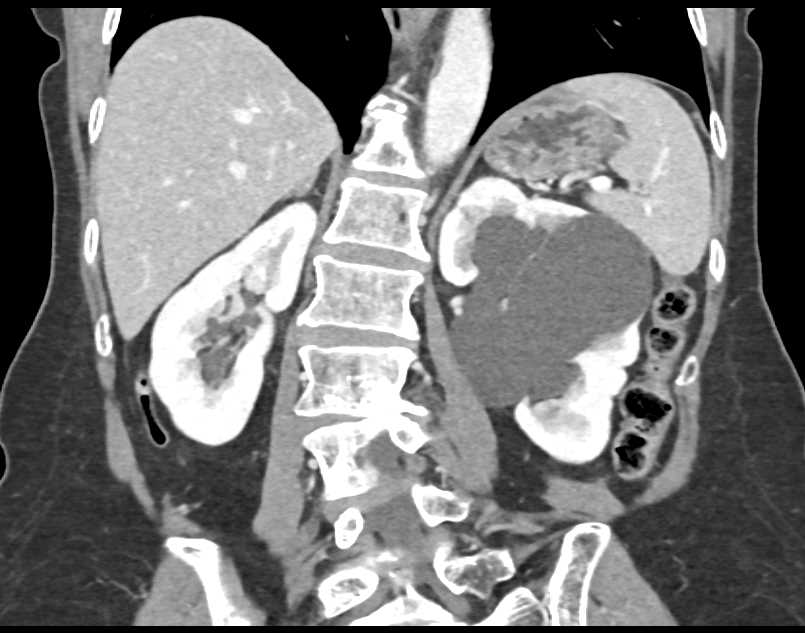

Parapelvic Cysts Left Kidney